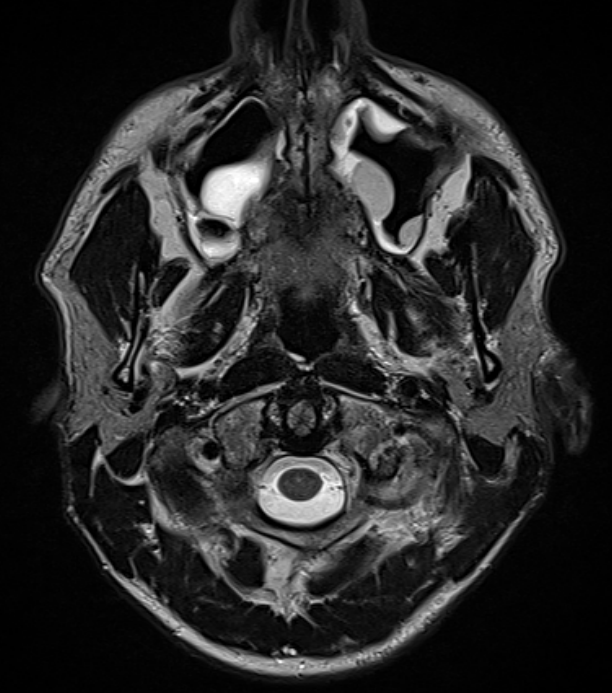

МРТ придаточных пазух носа

Магнитно-резонансная томография придаточных пазух носа – важный метод исследования, который позволяет оценить состояние придаточных пазух носа.